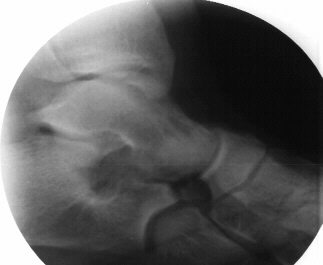

Radiographs - AP, lateral, oblique at 45 degrees, and Harris view. A coalition may be difficult to pick up on the AP and lateral views due to the overlap of bones but there may be some subtle clues. Beaking of the talus or narrowing of the subtalar joint may be present. Calcaneonavicular bony bridges can be seen on the lateral view with the classic "anteater nose" coming from the calcaneous. Harris view may be helpful to evaluate the subtalar joint but a CT is often obtained to rule out subtalar coalition. The ankle may remodel to a ball and socket joint secondary to limited subtalar motion. Coronal CT cuts are most helpful in evaluating talocalcaneal bony bridges while transverse cuts are used for calcaneonavicular bars.